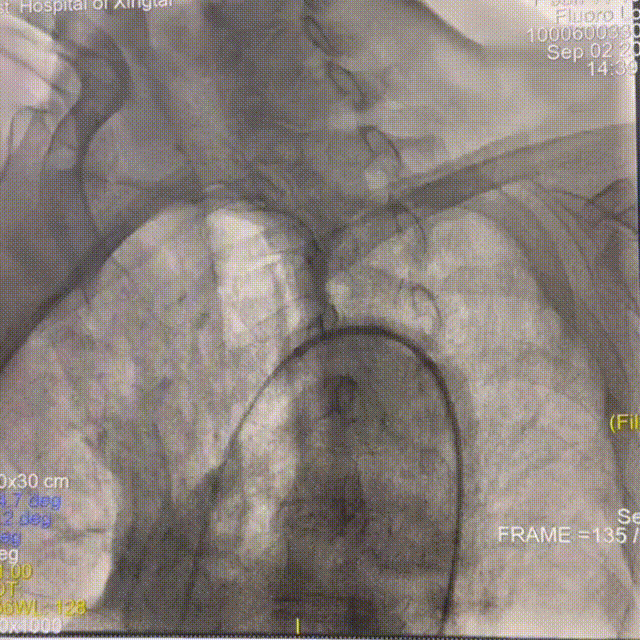

DSA提示患者右侧大脑中动脉狭窄率约95%;PWI提示右额颞顶叶低灌注。

动脉长鞘怎么置入一技之“长”丨经桡及经股困难入路应用赛诺神畅APEX TRA GC™导引导管建立通路病例合集_https://www.jmylbn.com_新闻资讯_第26张

头颅CT

动脉长鞘怎么置入一技之“长”丨经桡及经股困难入路应用赛诺神畅APEX TRA GC™导引导管建立通路病例合集_https://www.jmylbn.com_新闻资讯_第31张

动脉长鞘怎么置入一技之“长”丨经桡及经股困难入路应用赛诺神畅APEX TRA GC™导引导管建立通路病例合集_https://www.jmylbn.com_新闻资讯_第32张

头PWI

DSA